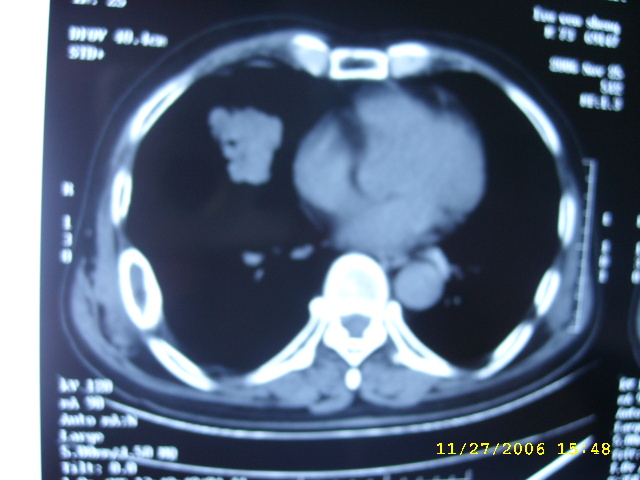

如果右肺病变与肋骨病变联系起来考虑:1右肺周围ca并肋骨转移;2:嗜酸性肉牙肿?

肺部病变先考虑周围性肺癌,肋骨病变不象破坏和转移,应考虑骨纤.一影论影.

1右肺周围ca

2骨纤维异常增埴症

肋骨应该不是转移,其为膨胀性改变,边缘增厚硬化,临近软组织未见明显异常改变,考虑骨纤等病变。

右侧周围型肺癌伴肋骨转移.

右侧肺癌,右侧肋骨转移?

肺部的病灶是比较肯定的,但肋骨骨质完整,未见破坏征象,故肋骨考虑骨纤维异常增殖症。

单纯肋骨局限性膨胀,边界清楚,皮质增生硬化,考虑:1  请详细了解病史,除外陈旧骨折.2 骨纤维异常增埴症

周围型肺癌.肋骨可能是陈旧骨折愈合.

右肺内病变考虑肺癌,右侧肋骨局部增粗,皮质增厚,髓腔增宽,有否陈旧骨折?先考虑骨纤维异常增殖症。

1.右下肺病灶周围型肺癌的可能性非常大。

2.右侧肋骨病变转移的可能性非常小,首先考虑骨母细瘤。次则考虑骨纤维异常增殖症。

建议详细询问病史,排除陈旧性骨折所致。

1.右侧周围型肺癌.

2.肋骨病变虑骨纤维异常增殖症.

肺部病变考虑周围性肺癌,肋骨病变考虑骨纤